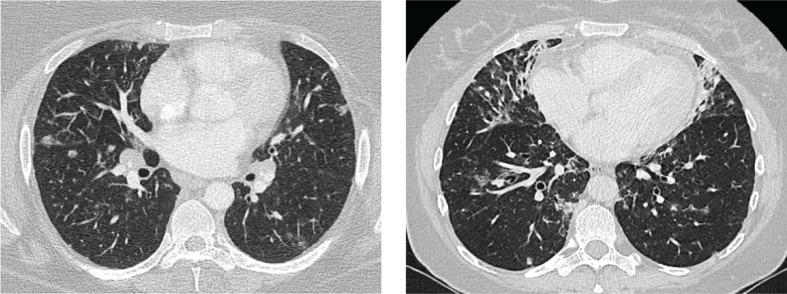

Granulomatous lymphocytic interstitial lung disease (GLILD) is present in about 20% of patients with common variable immunodeficiency disorders (CVID). GLILD is characterized by nodules, reticulation, and ground-glass opacities on CT scans. To date, large cohort studies that include sensitive CT outcome measures are lacking, and severity of structural lung disease remains unknown. The aim of this study was to introduce and compare two scoring methods to phenotype CT scans of GLILD patients.

肉芽肿性淋巴细胞性间质性肺病(GLILD)存在于约 20%的普通变异性免疫缺陷疾病(CVID)患者中。GLILD 的 CT 扫描特征为结节、网状影和磨玻璃影。迄今为止,缺乏包括敏感 CT 结果测量的大型队列研究,且结构性肺疾病的严重程度尚不清楚。本研究旨在介绍和比较两种用于表型 GLILD 患者 CT 扫描的评分方法。